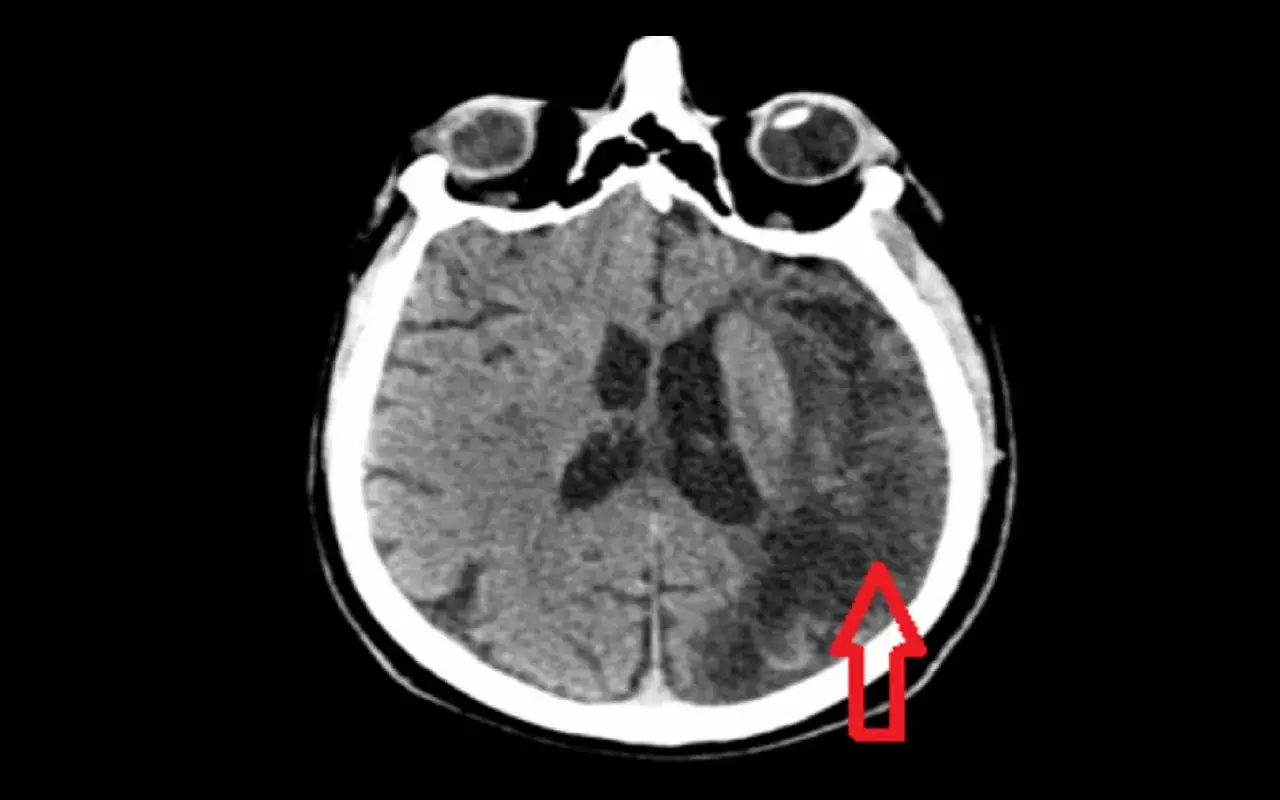

Udar krwotoczny (potocznie: wylew): gdy pęknięte naczynie zalewa mózg krwią (ok. 20% przypadków)

Ten typ udaru odpowiada za około 15-20% wszystkich przypadków. Jego mechanizm jest odwrotny do udaru niedokrwiennego: jest spowodowany pęknięciem ściany naczynia krwionośnego w mózgu. Krew wylewa się do tkanki mózgowej (krwotok śródmózgowy) lub do przestrzeni otaczającej mózg (krwotok podpajęczynówkowy). To właśnie ten typ udaru jest potocznie nazywany "wylewem". Główne przyczyny to:

- Wieloletnie, źle kontrolowane nadciśnienie tętnicze, które osłabia ściany naczyń.

- Pęknięcie tętniaka czyli patologicznego poszerzenia ściany naczynia.